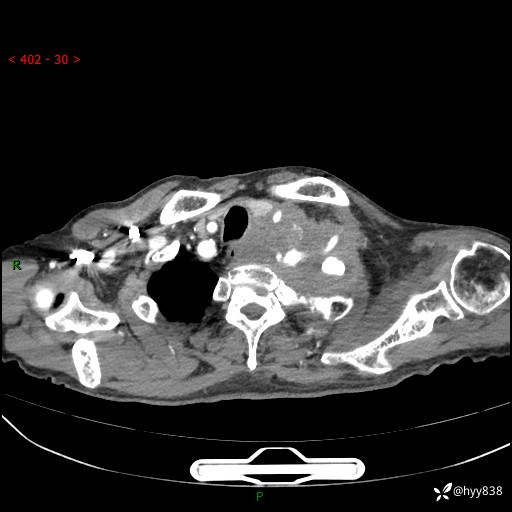

老年男性,气促5月,胸背痛2月。发现肺尖较大肿块,摧枯拉朽之势---结果公布~

现病史:患者于5月前饮酒后突发静息状态下气促不适,无胸闷、胸痛、发热、咳嗽、咳痰等不适,于当地第五人民医院及我院就诊,输液治疗后(具体不详)后气促稍缓解,遂出院后自行口服中草药治疗。近2月出现胸背痛,伴左上肢疼痛、乏力、感觉异常,稍有咳嗽、咳痰,咳黄痰、痰液粘稠,无咳血。为进一步诊治来我院。

胸部CT增强扫描(外院平扫)